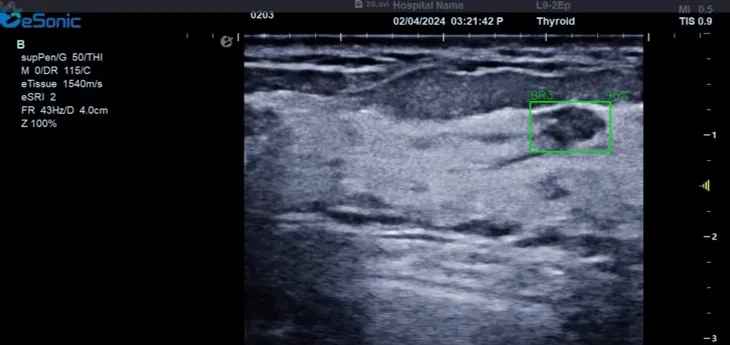

hjc888黄金城官网医疗(ESI)表示,其最新的人工智能功能可以帮助到医疗机构的工作效率,功能包括,实时、动态、快速自动识别病灶,良恶性病灶概率预测,甲状腺结节和乳腺的二维灰阶动态自动实时检测需求,提供多个结节动态检测轮廓框。实时获取多幅具备临床特征(大小、属性等)的结节切面,同时提供当前切面所示结节的结节大小、属性特征、TI-RADS 分级。

对于甲状腺结节相关的自动检测功能,甲状腺结节病灶检出率≥95%,良恶性分类灵敏度≥90%、良恶性分类特异度≥85%。